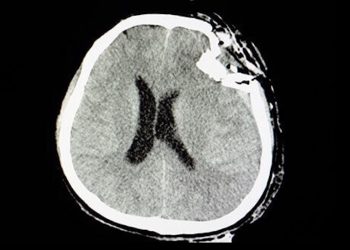

Schädel-Hirn-Traumata (SHT) werden in aller Regel durch Unfälle verursacht, besonders oft kommen sie bei uns durch Verkehrsunfälle zustande. Beinahe die ...